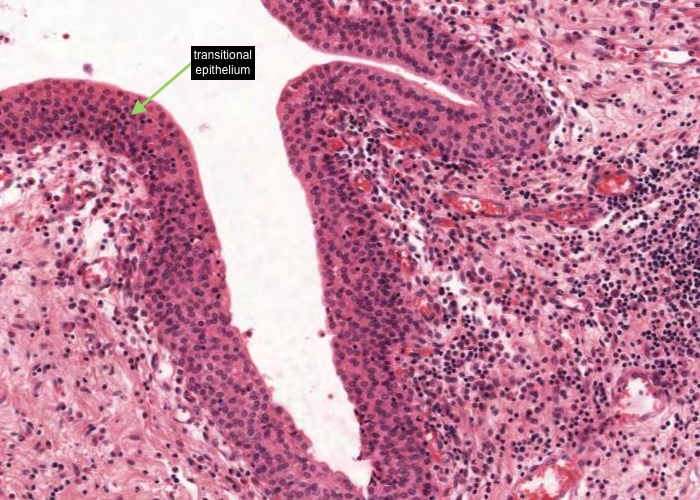

At low magnification, observe the three layers of the ureter: mucosa, muscularis and adventitia. This organization is maintained throughout the urinary passages. The mucosa of the ureter is thrown into characteristic longitudinal folds. It is made of transitional epithelium underlain by a layer of fairly cellular connective tissue (lamina propria). Quite a few lymphocytes are found in this lamina propria. The muscularis layer consists of two somewhat diffuse sheets of smooth muscle: the inner is longitudinal, and the outer is circular. Towards the bladder end it picks up a third oblique layer. This muscle produces peristaltic waves that push the urine to the bladder even when you are lying down. The adventitia is made of connective tissue and contains the nerves and blood vessels that supply the organ. One thing to note is that the ureter runs through loose connective tissue from the kidney to the bladder.

The ureter and also the other passages within the kidney through which urine flows i.e. the calyces and renal pelvis, are lined by transitional epithelium (often referred to as urothelium). The details of the layers of cells within this type of epithelium is best described in the later item "lumenal epithelium" of the bladder but generally it is 2-3 cell layers thick in the minor calyces but much thicker as you see here in the ureter and then the bladder.

Transitional epithelium is impermeable to water and salts and can accomodate the distension of the bladder as it fills with urine. In this image of "relaxed bladder" there are about 8 cell layers but make sure you notice how these layers "flatten out" in the "stretched bladder" image in the later item. Notice how the surface cells are cuboidal and bulge into the lumen of the bladder but their apex is curved or shaped like a dome so they are often referred to as "umbrella cells". The connective tissue below the epithelium is very cellular.